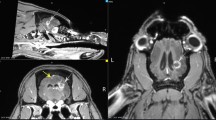

Rats were placed on a custom-made stereotactic frame fixed on a Kappa goniometer, by which the rat could be translated and rotated in front to the fixed horizontal X-ray beam. The spatial configuration of the microbeams was checked by gafchromic® films. Irradiations covered 4 mm on the rostrocaudal direction, from 1 mm anterior to 3 mm posterior to the bregma, in both irradiated groups (Fig. 5). Mediolateral irradiation covered a 1.5 mm span for the group receiving 360 Gy and a 4.2 mm span for group receiving 150 Gy.

Brain regions of rats irradiated with an array of 7 microbeam, 100 µm wide, and spaced by 400 µm with an incident peak dose of 360 Gy (left image) or an array of 4 minibeams, 600 µm wide and spaced by 1200 µm with an incident peak dose of 150 Gy (right image). Blue lines indicate the beam array. The irradiation extension in antero-posterior direction was 4 mm (1 mm anterior to −3 mm posterior to the bregma); in the medio-lateral direction, the microbeam array extension was respectively 1.5 and 4.2 mm for 360 Gy and 150 Gy, respectively. Images are taken from Paxinos and Watson rat atlas45.

Rats were randomly assigned to three different groups: 8 rats were irradiated with 7 microbeams, 100 μm wide, 400 μm centre-to-centre (c-t-c), with a skin entrance peak dose of 360 Gy and a valley dose of 5.3; 8 rats were irradiated with 4 “thick” microbeams, 600 μm wide and 1200 μm c-t-c with a skin entrance peak dose of 150 Gy and a valley dose of 6 Gy. An additional group of 8 rats was sham-irradiated and used as control group.